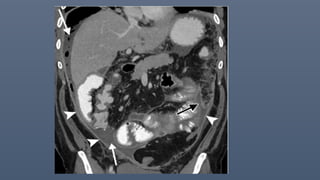

Encapsulating peritoneal sclerosis

and peritoneal carcinomatosis. Axial (A)

coronal (B) contrast-enhanced CT images

grouping of the small bowel loops (straight

white arrows in A) in the central portion of

the abdomen. The bowel loops appear to

be

encased in an abnormally thickened

peritoneum

(white arrowheads in A and B), with

anterior

displacement of the transverse colon

(curved

white arrow in A). Multiple metastatic

mesenteric

Encapsulating peritoneal sclerosis ina 77-year-old woman with ovarian cancer and peritoneal carcinomatosis. Axial (A) and coronal (B) contrast-enhanced CT images show grouping of the small bowel loops (straight white arrows in A) in the central portion of the abdomen. The bowel loops appear to be encased in an abnormally thickened peritoneum (white arrowheads in A and B), with anterior displacement of the transverse colon (curved white arrow in A). Multiple metastatic mesenteric